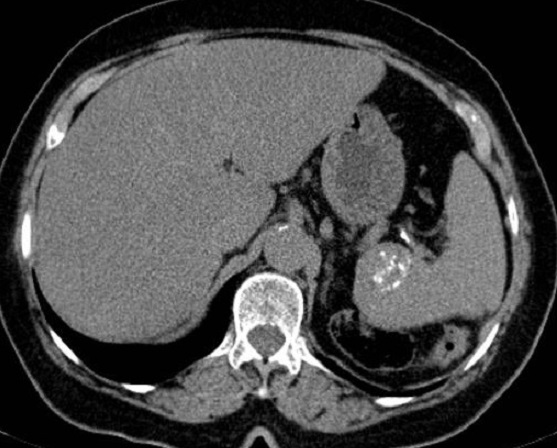

Image

radiologique TDM une rate surnuméraire à petite

taille situe au bord posterieure de la rate ( fléche

raouge ) . Aspect radiologique est une rate petite

homogène a bord nette , lisse , isodensité

retrosplenique |